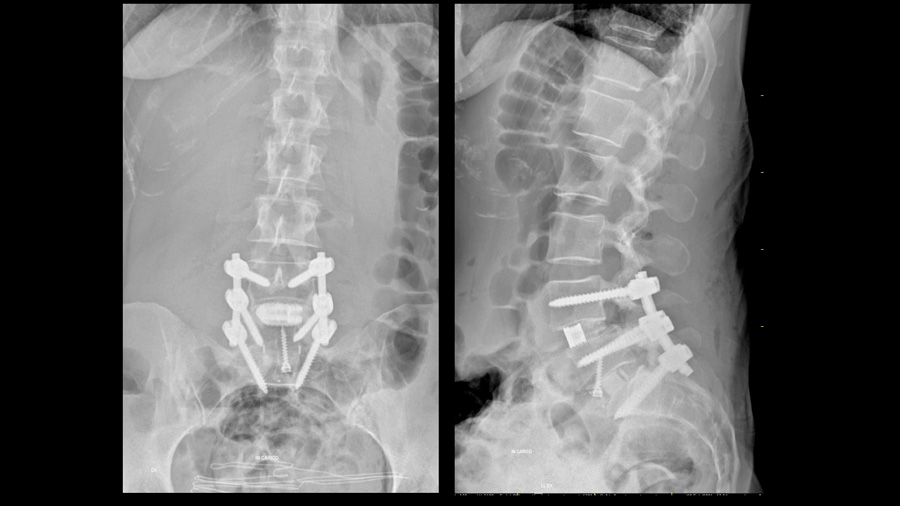

L5–S1 was treated with anterior lumbar interbody fusion (ALIF) to facilitate lordosis restoration. A 12-degree cage was used, with the acknowledgment that greater lordosis might have been achievable with a higher-angle implant. L4–5 was treated with posterior decompression and TLIF. Emphasis was placed on using a large, anteriorly positioned cage, posterior column osteotomy and compressing through the posterior column to maximize segmental lordosis.

Postoperative imaging demonstrated restoration of alignment and stable fixation from L4 to S1. However, what was particularly striking was the effect on the non-fused segments:

- The compensatory hyperlordosis at L3–4 decreased.

- Thoracic extension was reduced.

- The inflection point between thoracic kyphosis and lumbar lordosis migrated caudally.

These indirect changes illustrate a key concept of modern alignment surgery: successful correction allows the spine to abandon compensation. Compensation, while initially protective, is ultimately exhausting and mechanically costly. Removing the need for compensation may be as important as correcting the index pathology itself.

High pelvic incidence is typically associated with a steep sacral slope, which generates significant shear forces at the L5–S1 junction. This mechanical environment increases the risk of loosening and pseudarthrosis. In this patient, strategies to counteract these forces included bicortical S1 screws and a large-footprint interbody implant.

At 15-month follow-up, CT imaging confirmed a solid fusion. For the treating surgeon, this confirmation provided confidence in the durability of the result. In high PI patients, achieving reliable fusion is not an accessory goal; it is fundamental to the overall success of the operation.